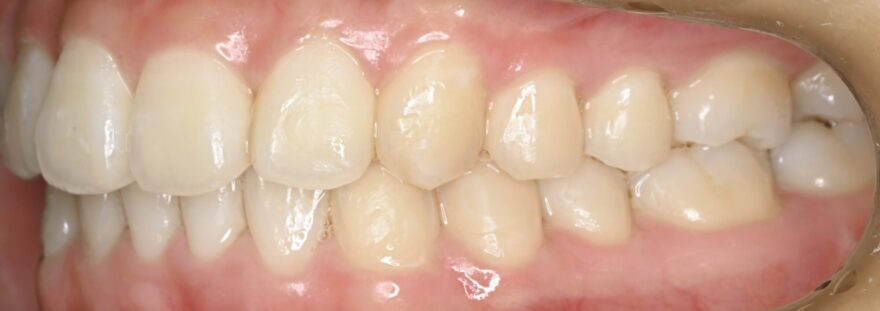

治療後の口腔内写真

約2年の動的期間(歯を動かす時期)で、ここまで整った歯並びになりました。

インビザラインでもワイヤー矯正でも、最終的な仕上がりに差はありません。

八重歯が完全に治りました。

前歯には後戻りを防止するための保定装置を装着しています。

下顎の前歯にもワイヤーによる保定装置を装着しています。